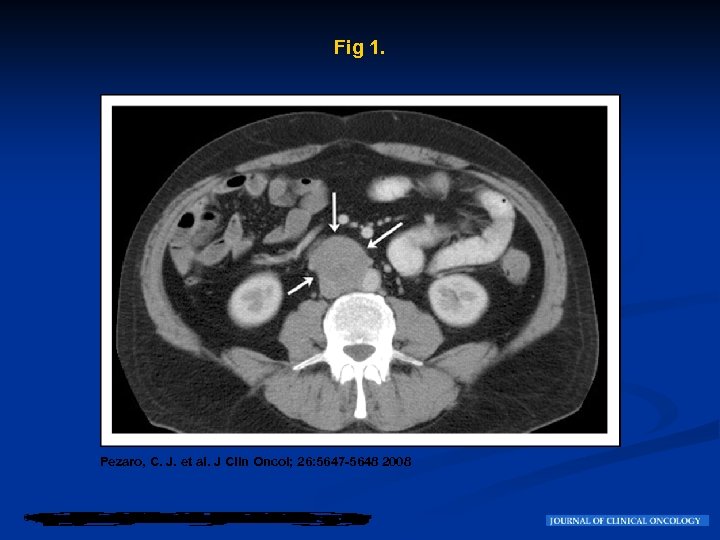

Evolución Esta masa fue biopsiada y mostró NSGCT. n Fue referido a nuestro Centro para su posterior manejo. Se realizó una tomografía por emision de Positrones (FDG-PET) que mostró una avidez a la captación de una masa ganglionar en el nivel de L 3 en los ganglios interaortocavos con una extensión caudal por debajo de la cadena de ganglios (Fig 2 A). Figure 2 B muestra claramente la localización interaortocavo posterior de la masa tumoral. n

Fig 2. Pezaro, C. J. et al. J Clin Oncol; 26: 5647 -5648 2008